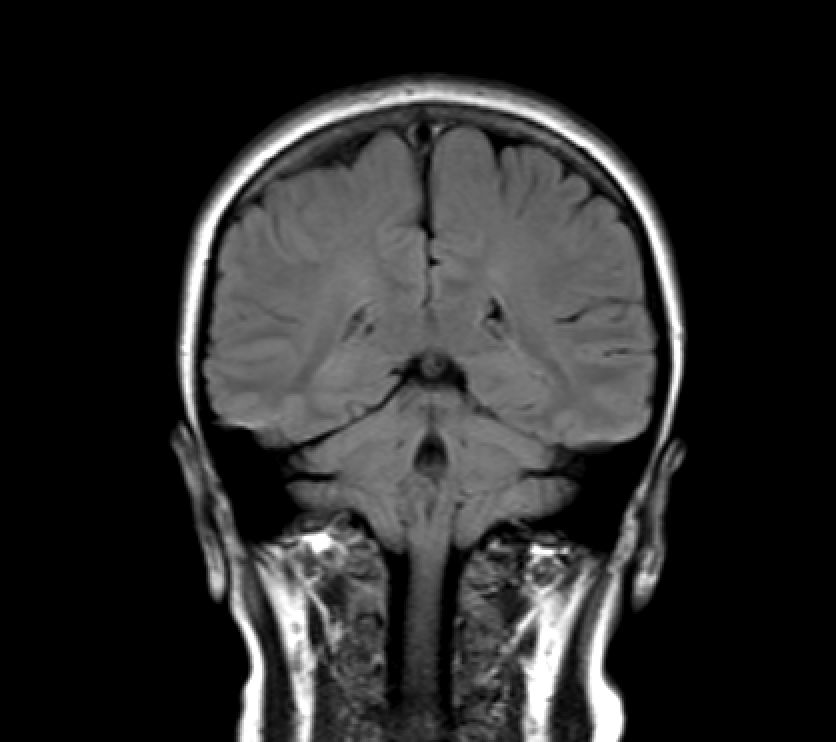

I have an MRI scan of my brain because some doctors wanted a closer look at it. Either I am a raving lunatic, or because I have a remarkable brain. One – or both.

- coronal

The point though, is that this is done in three axes: axial, saggital, coronal. So you can generate a 3D model that have three axes to average from, instead of one – meaning that the 3D model will not look like it was built from lego. As it would, if it only was one axis. I swear, i will 3D-print my brain when I get my head around the software.